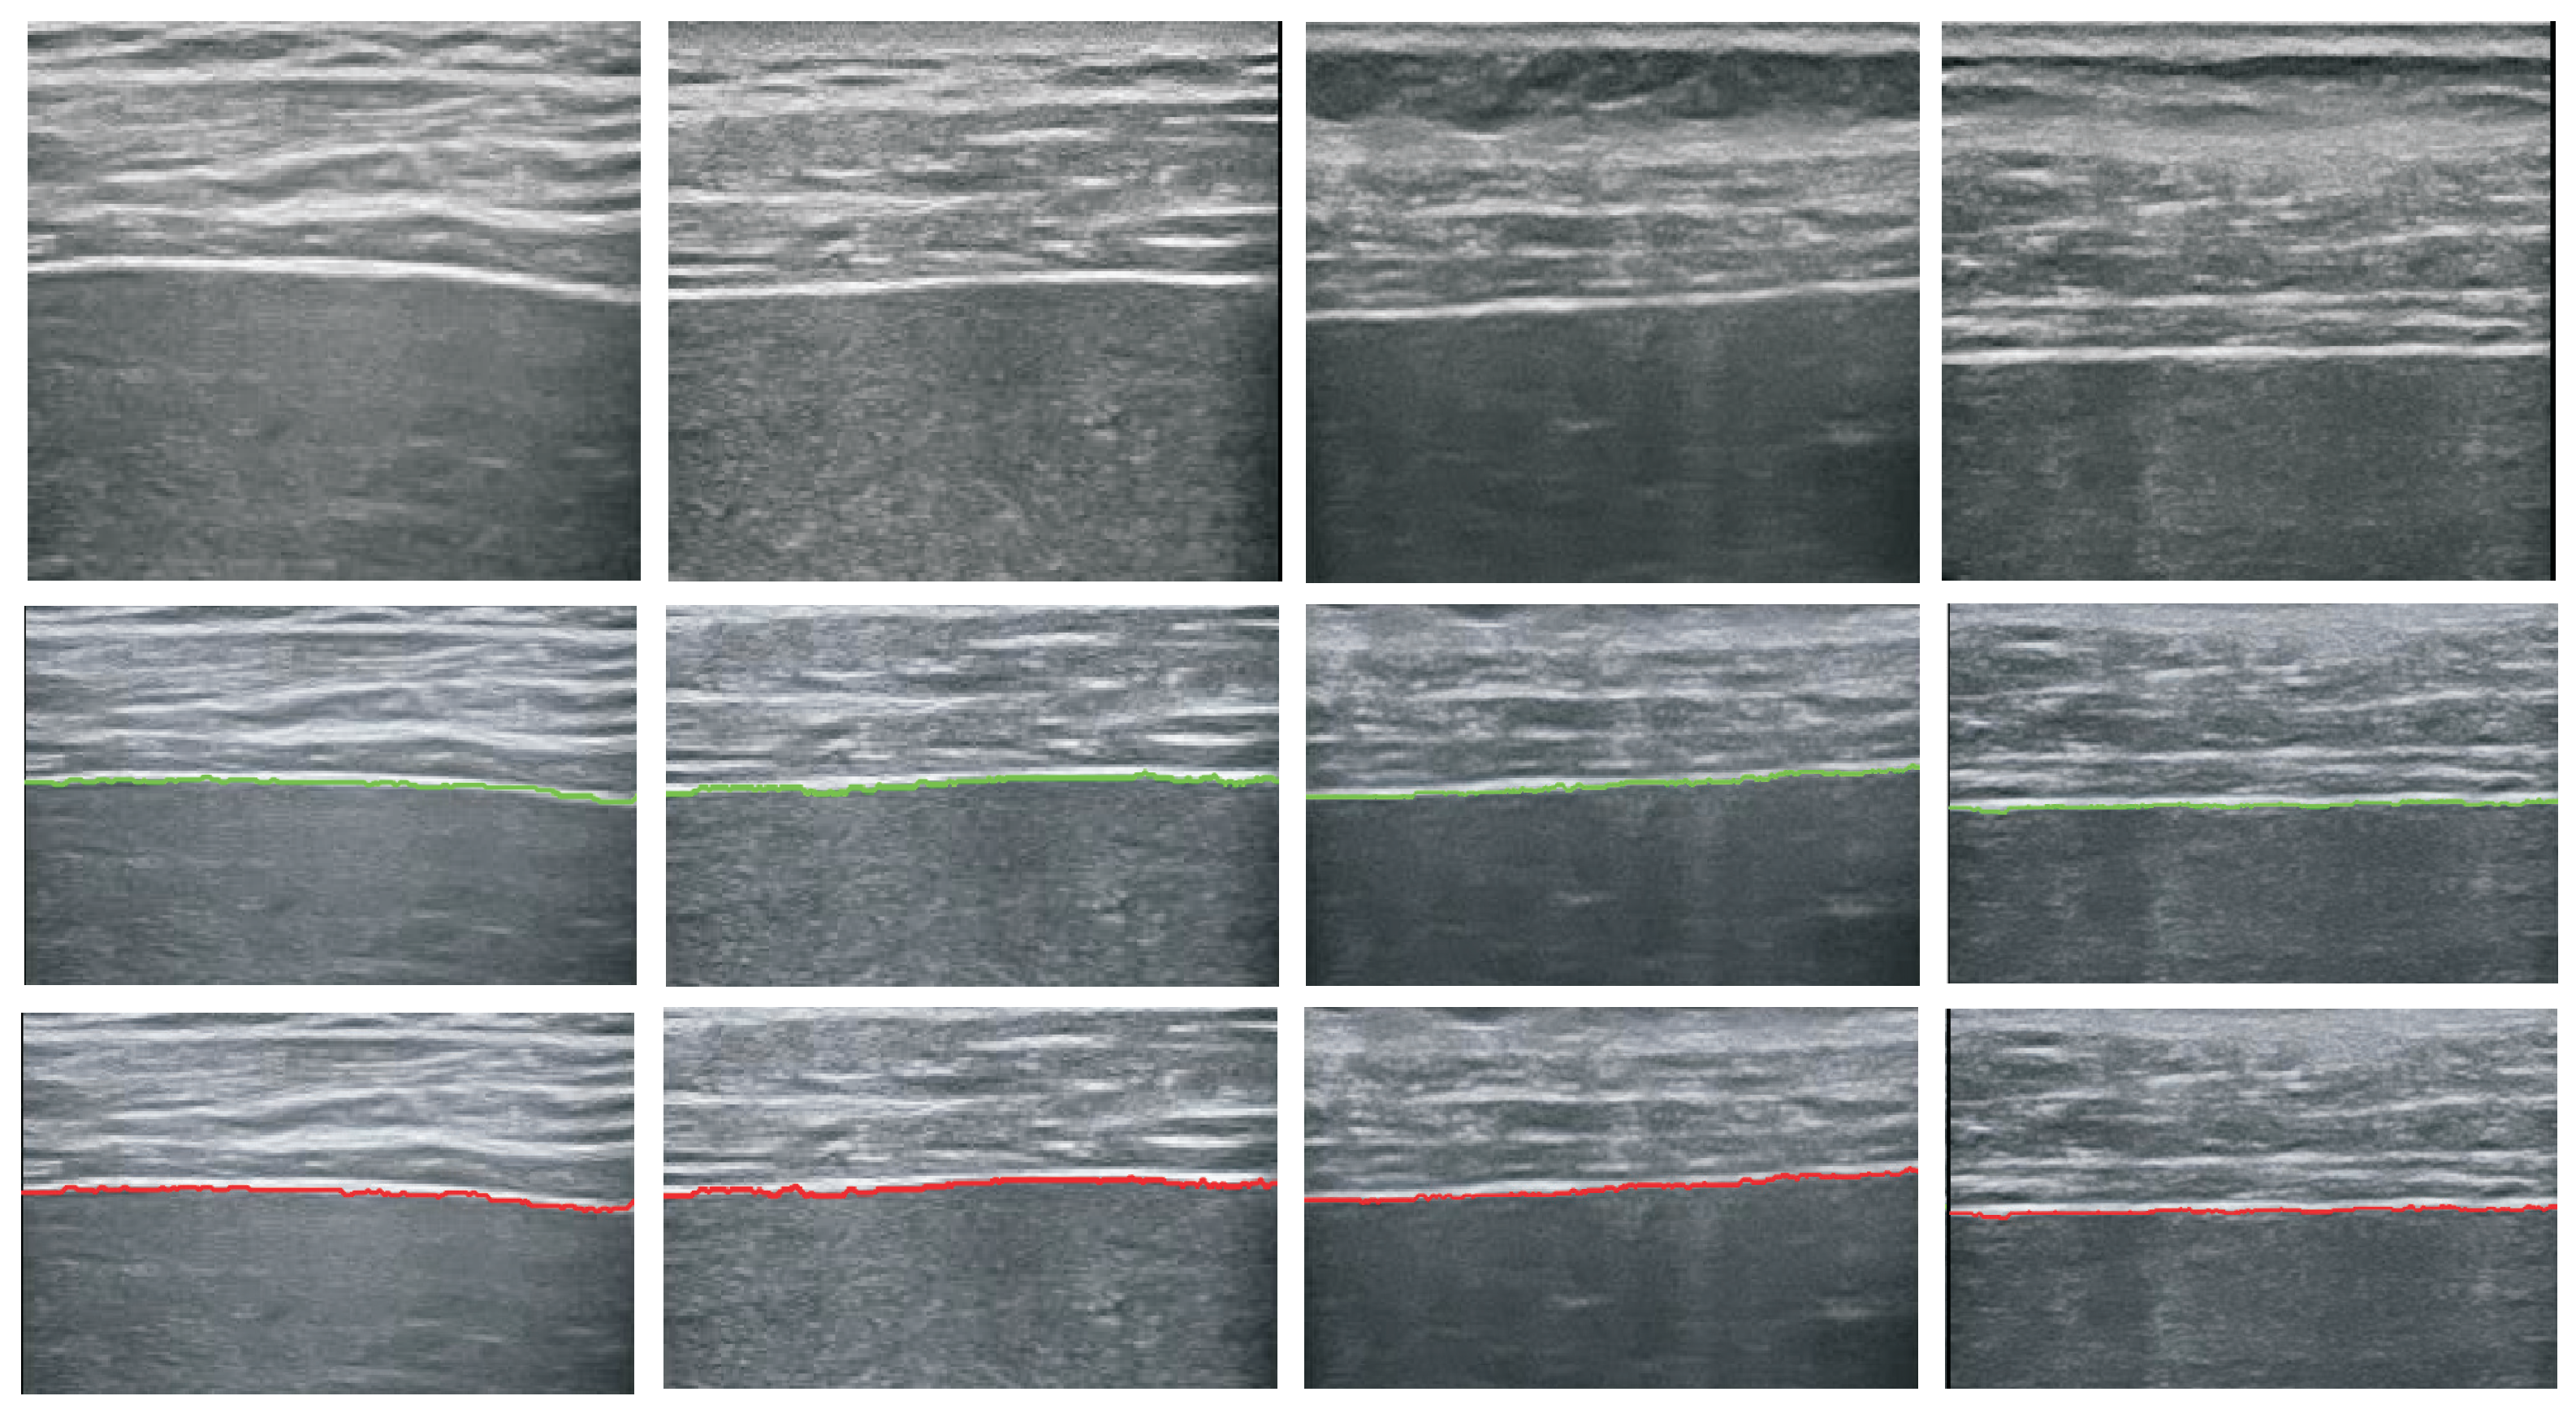

5.1. Performance of the Detector